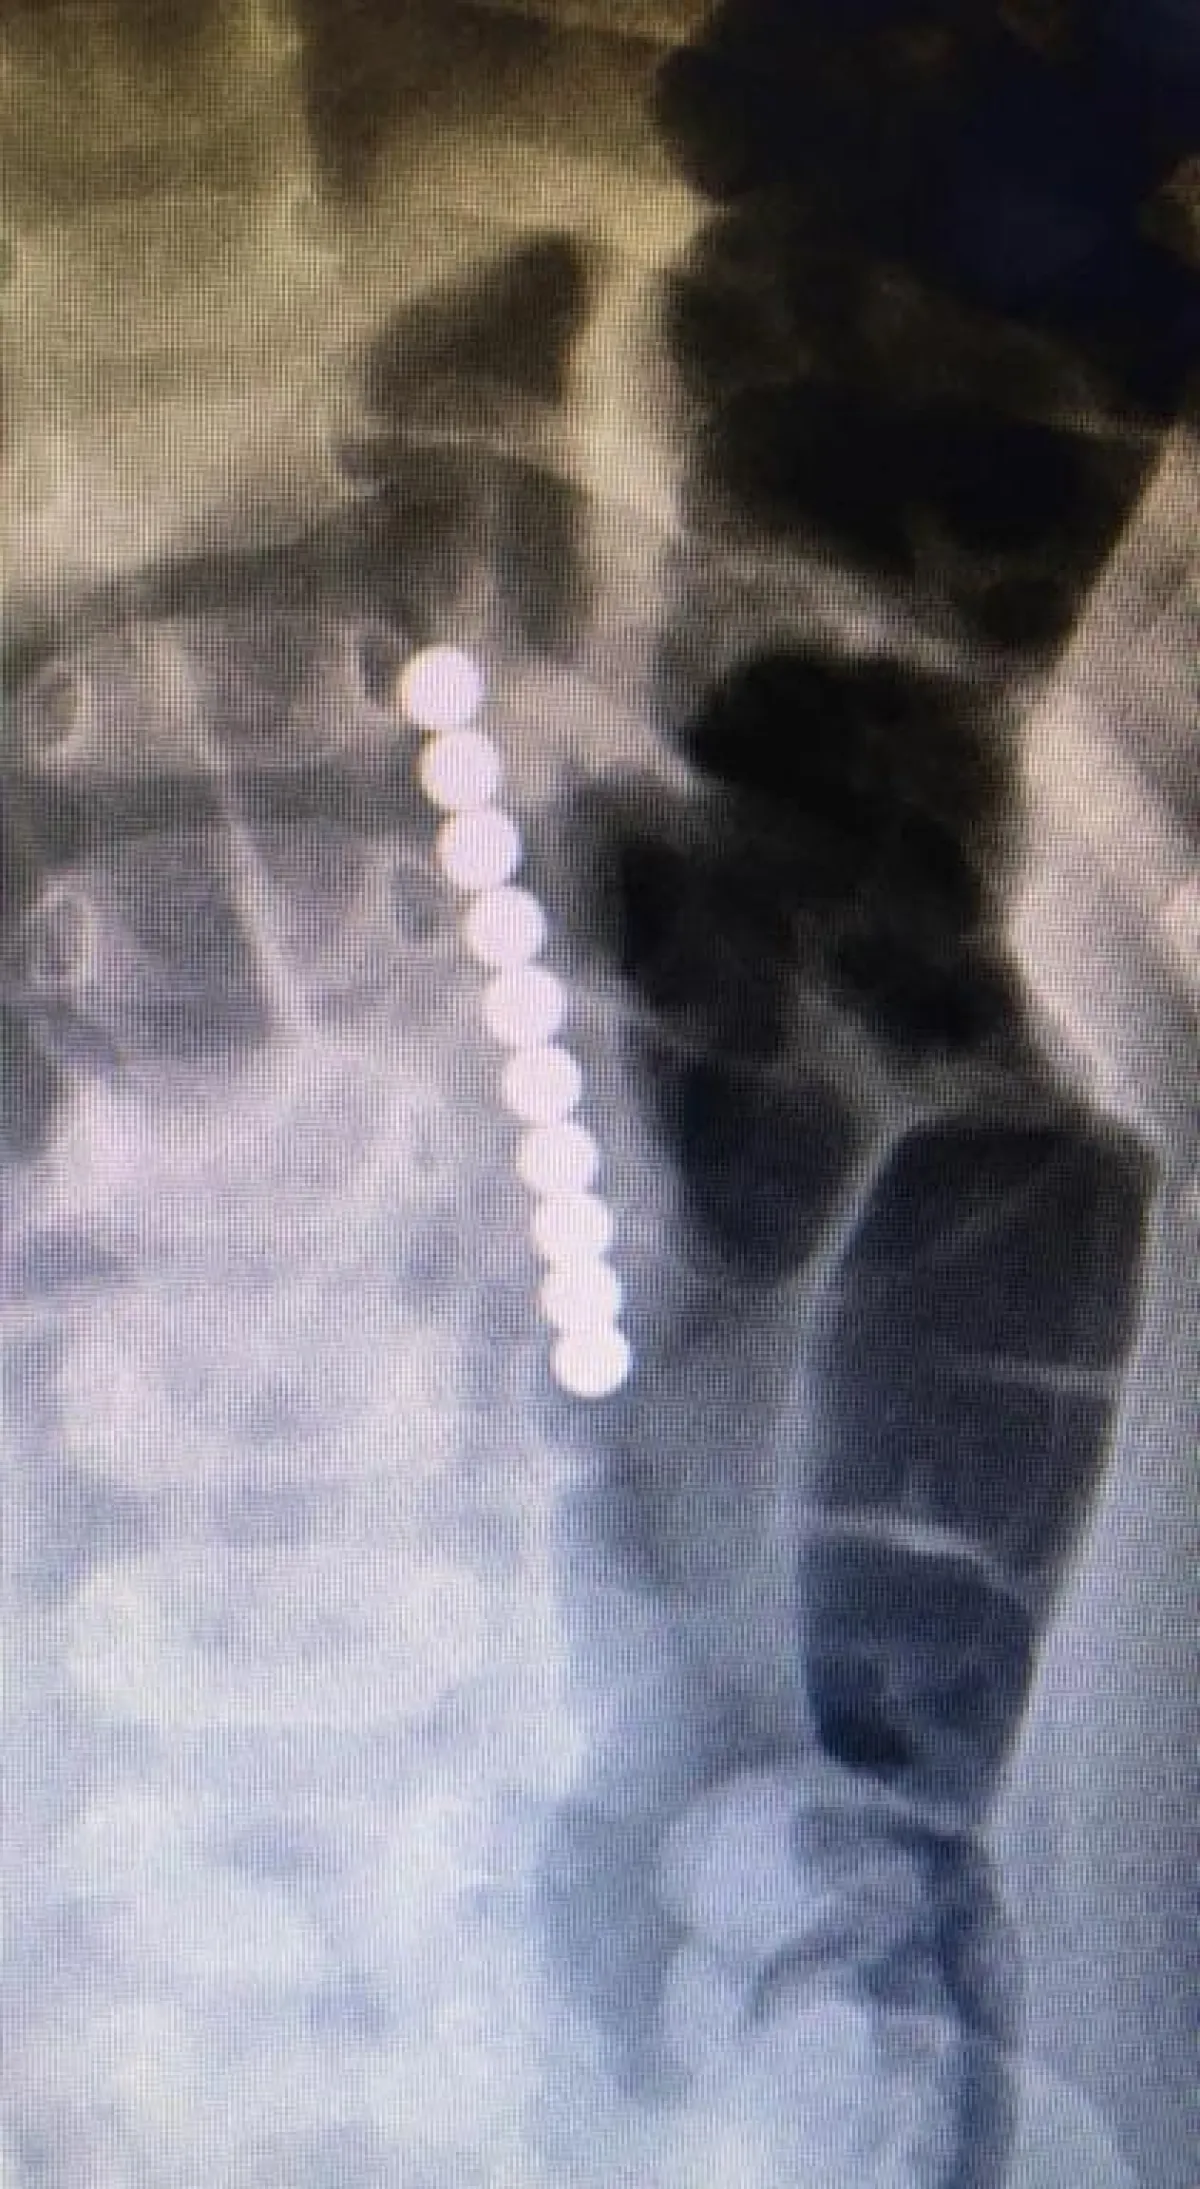

تمكَّن فريق طبي، يتكوَّن من أربعة أطباء في مستشفى الولادة والأطفال بالأحساء أمس من استخراج "سبحة مغناطيسية" من داخل بطن طفلٍ، يبلغ عامين من العمر.

وكان الطفل يعاني من قيء متكرر، وآلام حادة في البطن، وبعد إجراء الفحص الطبي والتحاليل والأشعة اللازمة، اتضح ابتلاعه "سبحة مغناطيسية"، سبَّبت له ثقوباً عدة داخل المعدة والأمعاء الدقيقة، فقرَّر الفريق الطبي إجراء عملية جراحية عاجلة له، وحقاً تم استخراج السبحة من بطنه، وإصلاح الثقوب، وغادر الطفل المستشفى بصحة جيدة.